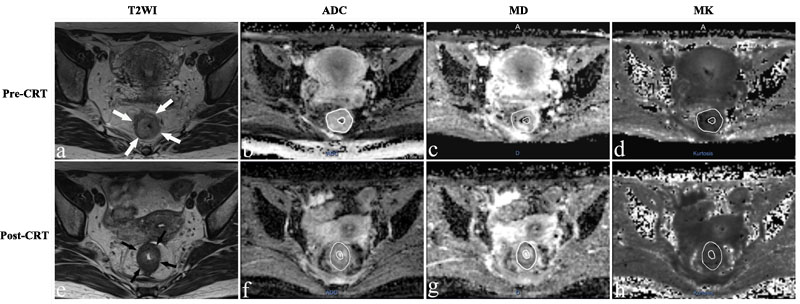

The population was consisting of 56 patients (16 females, 40 males) with an average age of 52.1±11.4 years. Fourteen patients showed pCR (Figure 1), whereas 42 patients were classified as non-pCR (Figure 2).

Figure 1: Representative images of a 36-year-old woman with a pCR. Images in each row are from two measurement time points: 2-5 days before CRT (pre-CRT) and 1-4 days before surgery (post-CRT). a., e. Before and after CRT T2-weighted MR image shows that there is a tumor with ring shape visible in the rectum (arrows). The ADC map, D map, and K map have similar image contrast and manual tracing of ROIs within the tumor area (The whole tumor was not shown here). The ADC, MD and MK values were 0.932×10-3 mm2/s, 1.580×10-3 mm2/s and 0.657 before treatment. The ADC and MD values increased obviously to 1.240×10-3mm2/s and 2.601×10-3mm2/s, while the MK value decreased slightly to 0.535 after CRT.